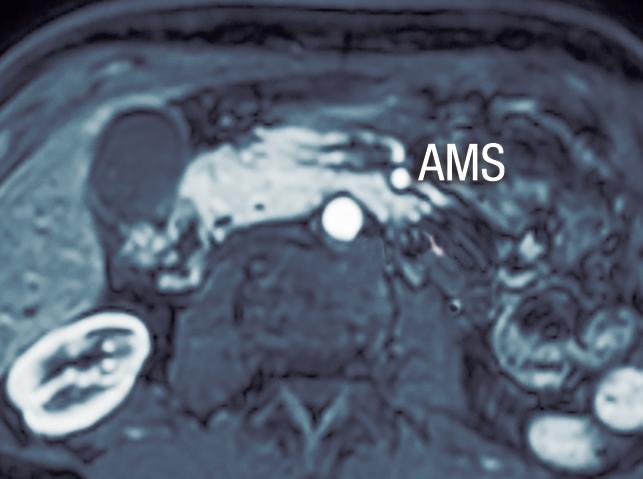

Hipoplasia pancreática

La agenesia pancreática completa es incompatible con la vida y extremadamente infrecuente. La agenesia parcial o hipoplasia puede involucrar el brote ventral o dorsal, con mayor frecuencia este último. Puede ser una condición aislada o bien estar asociada al síndrome de heterotaxia - poliesplenia. En la hipoplasia del páncreas dorsal se observa la porción cefálica y el proceso uncinado de aspecto redondeado, con ausencia del cuello, cuerpo y cola. Suele observarse relativa prominencia

del proceso uncinado, que se prolonga por detrás de los vasos mesentéricos (Figura 15). Es imprescindible efectuar el diagnóstico diferencial y descartar exhaustivamente una lesión neoplásica que provoque atrofia del páncreas corpocaudal, distal al tumor. Los individuos con agenesia del páncreas dorsal suelen ser asintomáticos, aunque se ha descripto un riesgo incrementado de padecer diabetes debido a que el mayor porcentaje de los islotes de células de Langerhans se hallan en el páncreas distal. 27

parcial del brote dorsal)

A) Resonancia magnética, secuencia T2, plano coronal. Se observa un páncreas “truncado”, con ausencia de tejido glandular a la izquierda del cuello (flecha), coincidente con una agenesia parcial del brote embriológico dorsal. La cabeza de flecha nos muestra a la porción cefálica prominente, redondeada. B) Resonancia magnética, secuencia T1 con contraste, plano axial. Flecha: Limite de finalización de la glándula, a la izquierda de la arteria mesentérica superior. Cabeza de flecha: Porción cefálica prominente, redondeada. C) Resonancia magnética, secuencia T1 con contraste, plano axial, corte más caudal. Las flechas muestran hipertrofia relativa del proceso uncinado (brote ventral), el cual llega a ubicarse por detrás de los vasos mesentéricos superiores, incluso superando el plano de la arteria. AMS: arteria mesentérica superior.